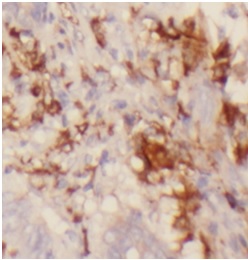

Immunohistochemistry of paraffin-embedded human colon cancer using FNab10130(ST6GAL1 antibody) at dilution of 1:200 IP Result of anti-ST6GAL1 (IP:FNab10130, 4ug; Detection:FNab10130 1:600) with Raji cells lysate 2000ug.